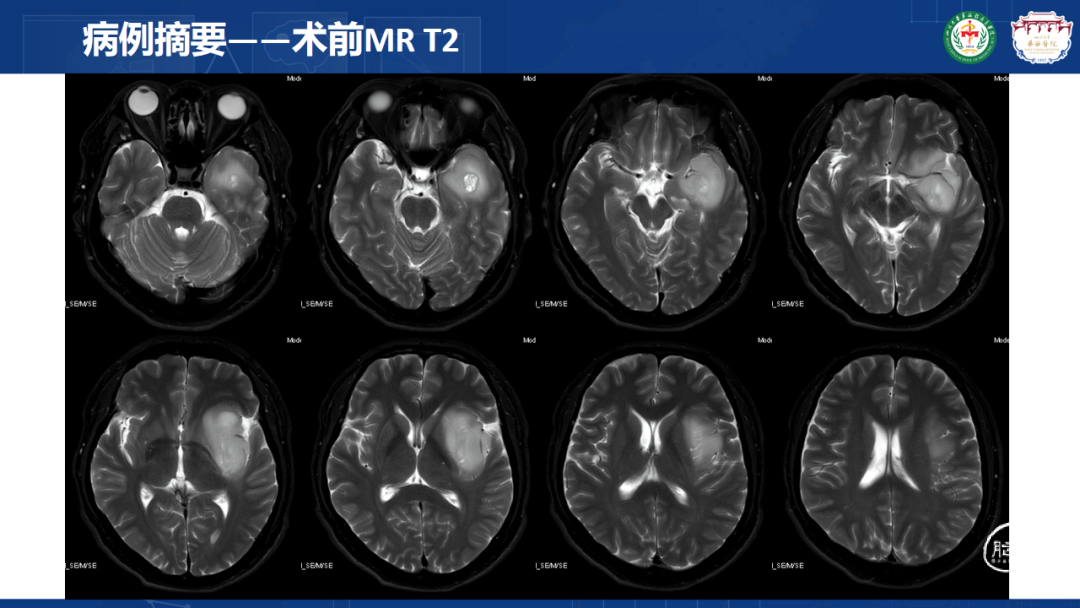

来自四川大学华西医院的曾云辉医师带来《岛叶胶质瘤手术及综合治疗》。该病例是一名41岁男性IT从业者,表现为头晕、右侧肢体麻木伴幻听,MRI显示左侧额颞岛叶占位累及海马头,DTl重建显示肿瘤包绕大脑中动脉分支。术中使用无牵拉技术联合多模态监测,经颞叶皮层造瘘切除病灶,术中重点保护侧裂静脉及M2段穿支血管。术后病理确诊为IDH突变型少突胶质细胞瘤(WHO 3级),规范实施同步放化疗联合6周期替莫唑胺辅助化疗。随访显示肿瘤控制良好,患者神经功能完整并恢复工作。